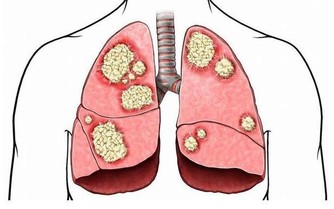

眾所周知,愛滋病是一個危害性極大的傳染病,是由於感染上愛滋病病毒(HIV)而引起的,死亡率很高。有數據表明,全球至少已有3千多萬人死於愛滋病,由此可見愛滋病威力之大。

目前,在全世界範圍內仍缺乏根治HIV感染的有效藥物,也無預防艾滋病的有效疫苗,因此最重要的是採取預防措施,其方法是: